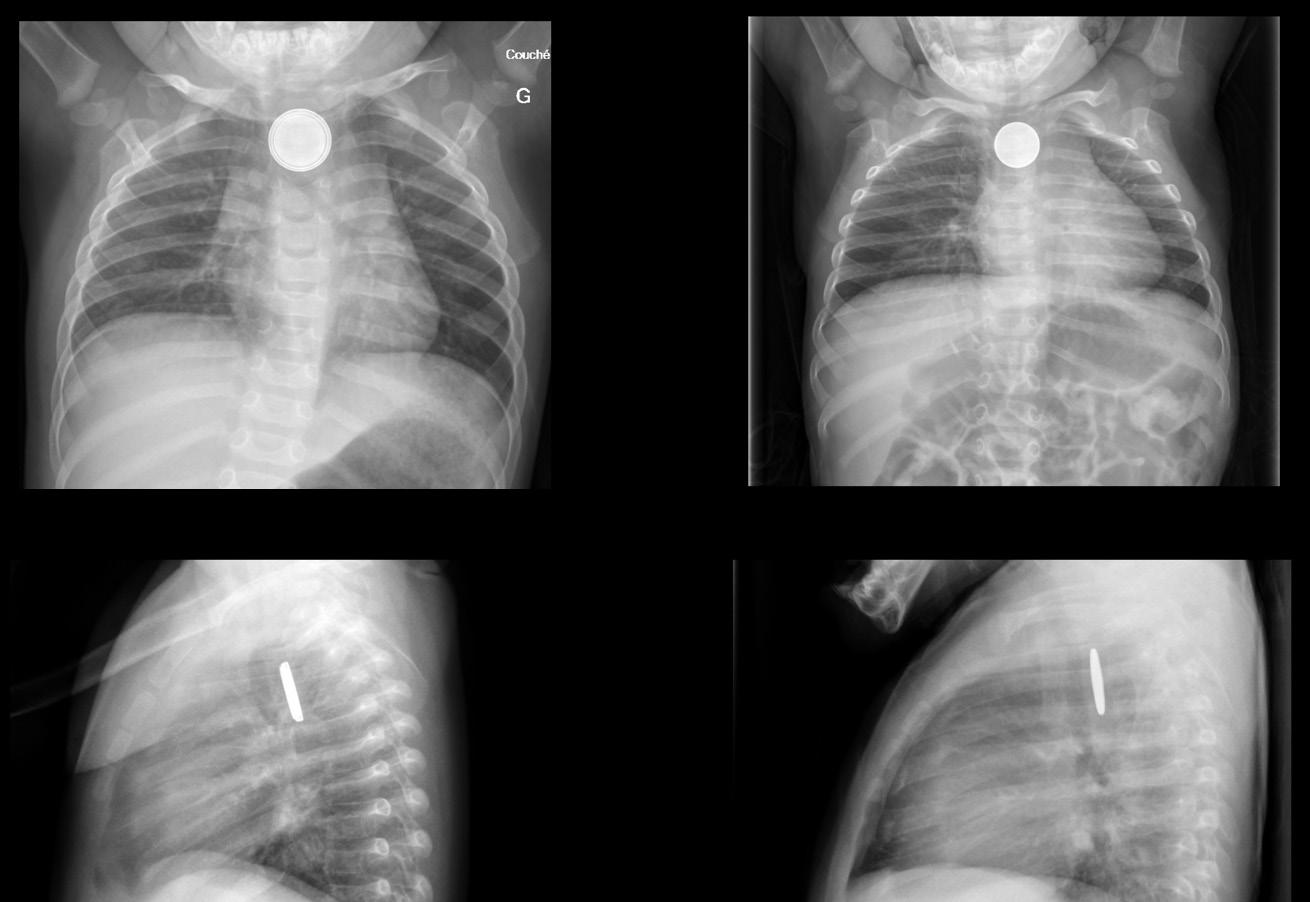

À son arrivée, nous constatons un enfant en bon état général, mais qui présente une hypersalivation et se plaint de douleurs rétrosternales; les signes vitaux sont normaux. Une radiographie thoracique est demandée en toute urgence et démontre la présence d’un objet arrondi au tiers moyen de l’œsophage. Nous organisons une endoscopie digestive sous anesthésie générale qui permet de retirer une pile bouton de 20 mm de diamètre. Lors de la procédure, on note déjà une zone importante d’érythème en regard de l’emplacement du corps étranger avec un ulcère superficiel et des zones de nécrose.

3PILE BOUTON VERSUS PIÈCE DE MONNAIE

Pile bouton Pièce de monnaie

En l’absence de témoins, le grand défi devant un enfant présentant un objet arrondi sur la radiographie thoracique est de distinguer une pièce de monnaie d’une pile bouton.

La figure 3 montre les nuances de présentation entre les deux types d’objets. Sur une vue frontale, les pièces de monnaie présentent un simple contour contrairement aux piles boutons qui ont un double contour. Sur la vue de profil, les pièces de monnaie ont un aspect biconvexe alors que les piles boutons ont une face plate et une autre légèrement convexe. Dans le cas des piles très fines, ces particularités radiologiques peuvent être moins évidentes.